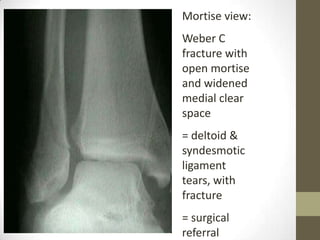

Mortise view:

Weber C

fracture with

open mortise

and widened

medial clear

space

= deltoid &

syndesmotic

ligament

tears, with

fracture

= surgical

referral